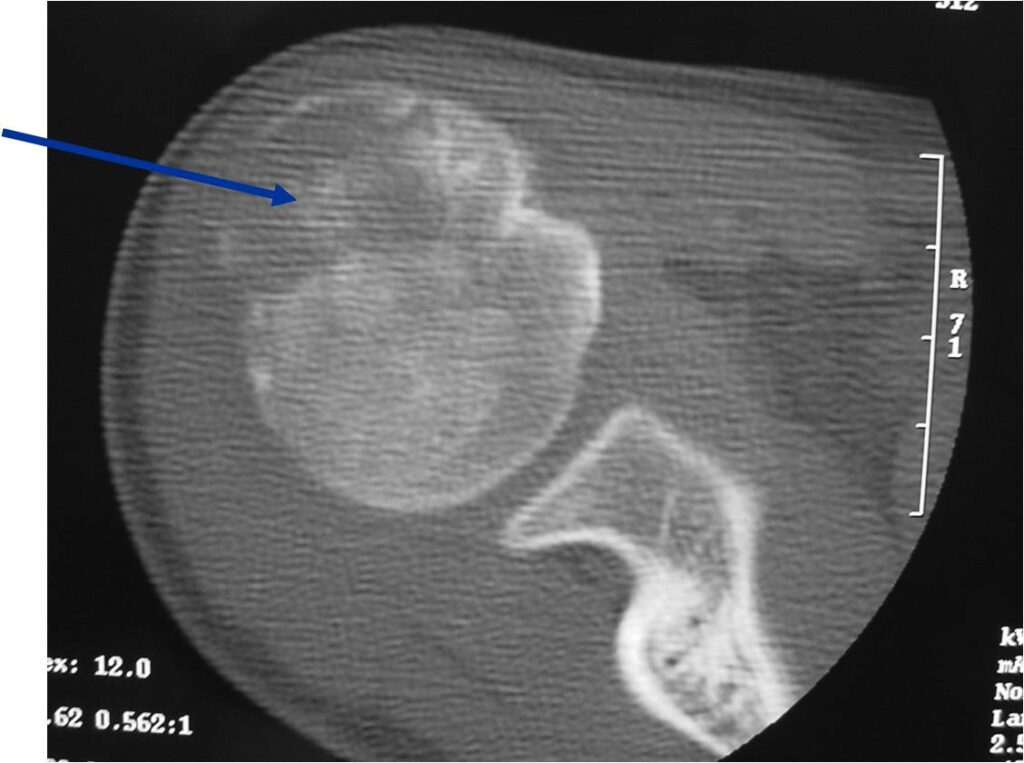

CT appearance:

- Most useful for detecting subtle mineralization not apparent on X-rays

- Useful for identifying intact periosteum around any expansile soft tissue component

- surrounding thin reactive shell of bone/mineralization (Egg Shell Rim of Calcification)

- helps place the tumor in a benign category

- helps evaluate:

- bony quality

- extent of bone and cortical destruction

- whether the subchondral plate of bone adjacent to the articular cartilage has been destroyed or is intact